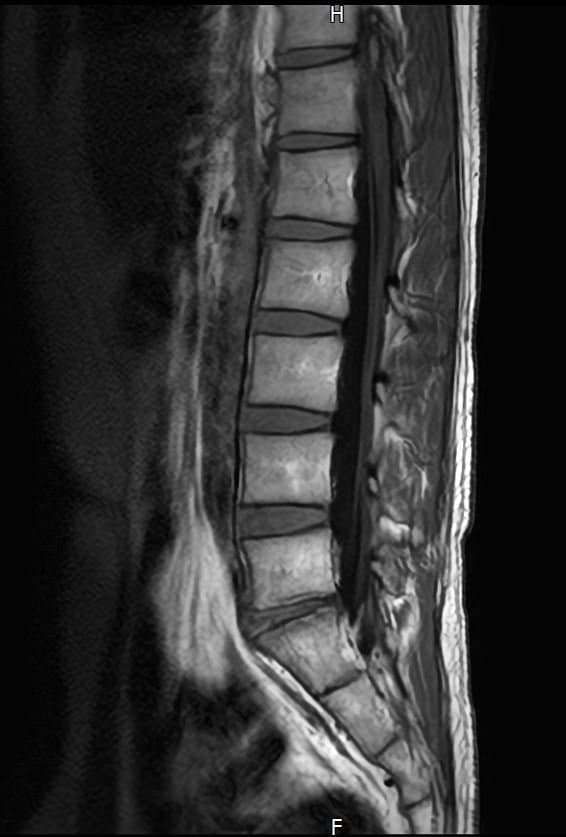

양쪽 엉덩이 염좌 6주째인데 mri 촬영한것좀 봐주세요

엉덩이 양쪽 염좌가 6주됨

방사통 없음 저림 없음 재채기 , 계단타기 전부 정상 , 숙일때 통증 없음

엉덩이 위쪽 바깥쪽 부분이 아픔 압통점 있음

177 / 66kg 약간의 퇴행성이 보인다는데 엉덩이 염좌와는 연관 없을꺼라고 하는데

영상과 증상을 종합해보면 전체적으로 척추배열은 양호하나, 요추4~5번과 요추5번~천추1번 사이의 디스크 수핵이 약간 검게 변한 퇴행성 변화가 관찰됩니다. 다만 신경을 심하게 압박하는 추간판탈출증 소견은 뚜렷하지 않습니다.현재 방사통이나 저림이 없고 특정부위에만 압통이 있다면 의료진의 소견대로 허리디스크보다는 근육 몇 인대문제일 가능성이 높습니다.말씀하신 부위는 염좌로 인해 예민해진 근막이나 인대가 완전히회복되지 않아 컨디션에 따라 통증이 반복될수 있습니다. 6주째 통증이 반복된다면 단순 휴식보다는 물리치료나 도수치료를 통해 굳어있는 근막을 풀어주는 것이 회복에 도움이 됩니다. 빠른쾌유를 빕니다!

MRI 영상상 관절 주변 조직의 부종이나 구체적인 염증 부위를 세밀하게 확인하는 과정이 꼭 필요해 보입니다.